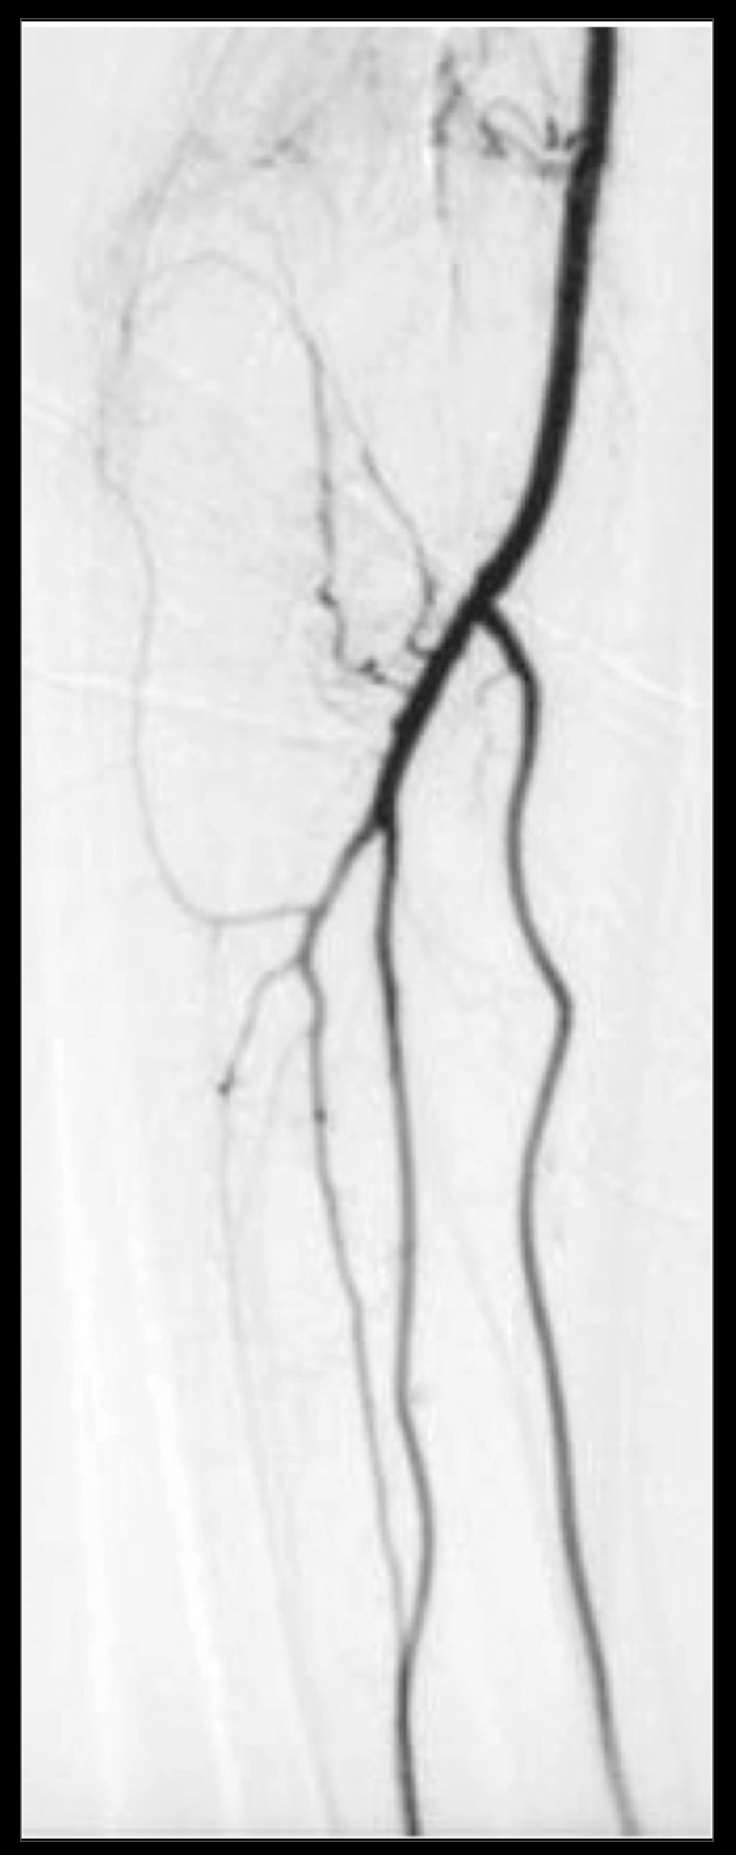

Essay answers are to be written in prose during the assigned examination time. Please write your answers in the spirit of communicating to a colleague or a knowledgeable patient. Demonstrate your understanding of anatomy more so than your rote memorization. If you draw a figure, please describe what you have drawn using anatomical terminology. Our aspirations for you are that you write the cookbook, not follow it.

1. A patient complains of shoulder pain and difficulty rotating their arm. An ultrasound reveals edema within the spinoglenoid notch, which could explain weakness in external rotation at the glenohumeral joint. Describe the normal scapular and shoulder anastomosis, including all arterial branches involved and their relationship to any ligaments, scapula borders, and intermuscular spaces. If the axillary a. is ligated immediately distal to the thyrocervical trunk, would this edema affect active collateral circulation? (If yes, explain.) Also, include a brief (2-3 sentences) explanation for why edema within the spinoglenoid notch might result in weak external/lateral rotation of the shoulder.